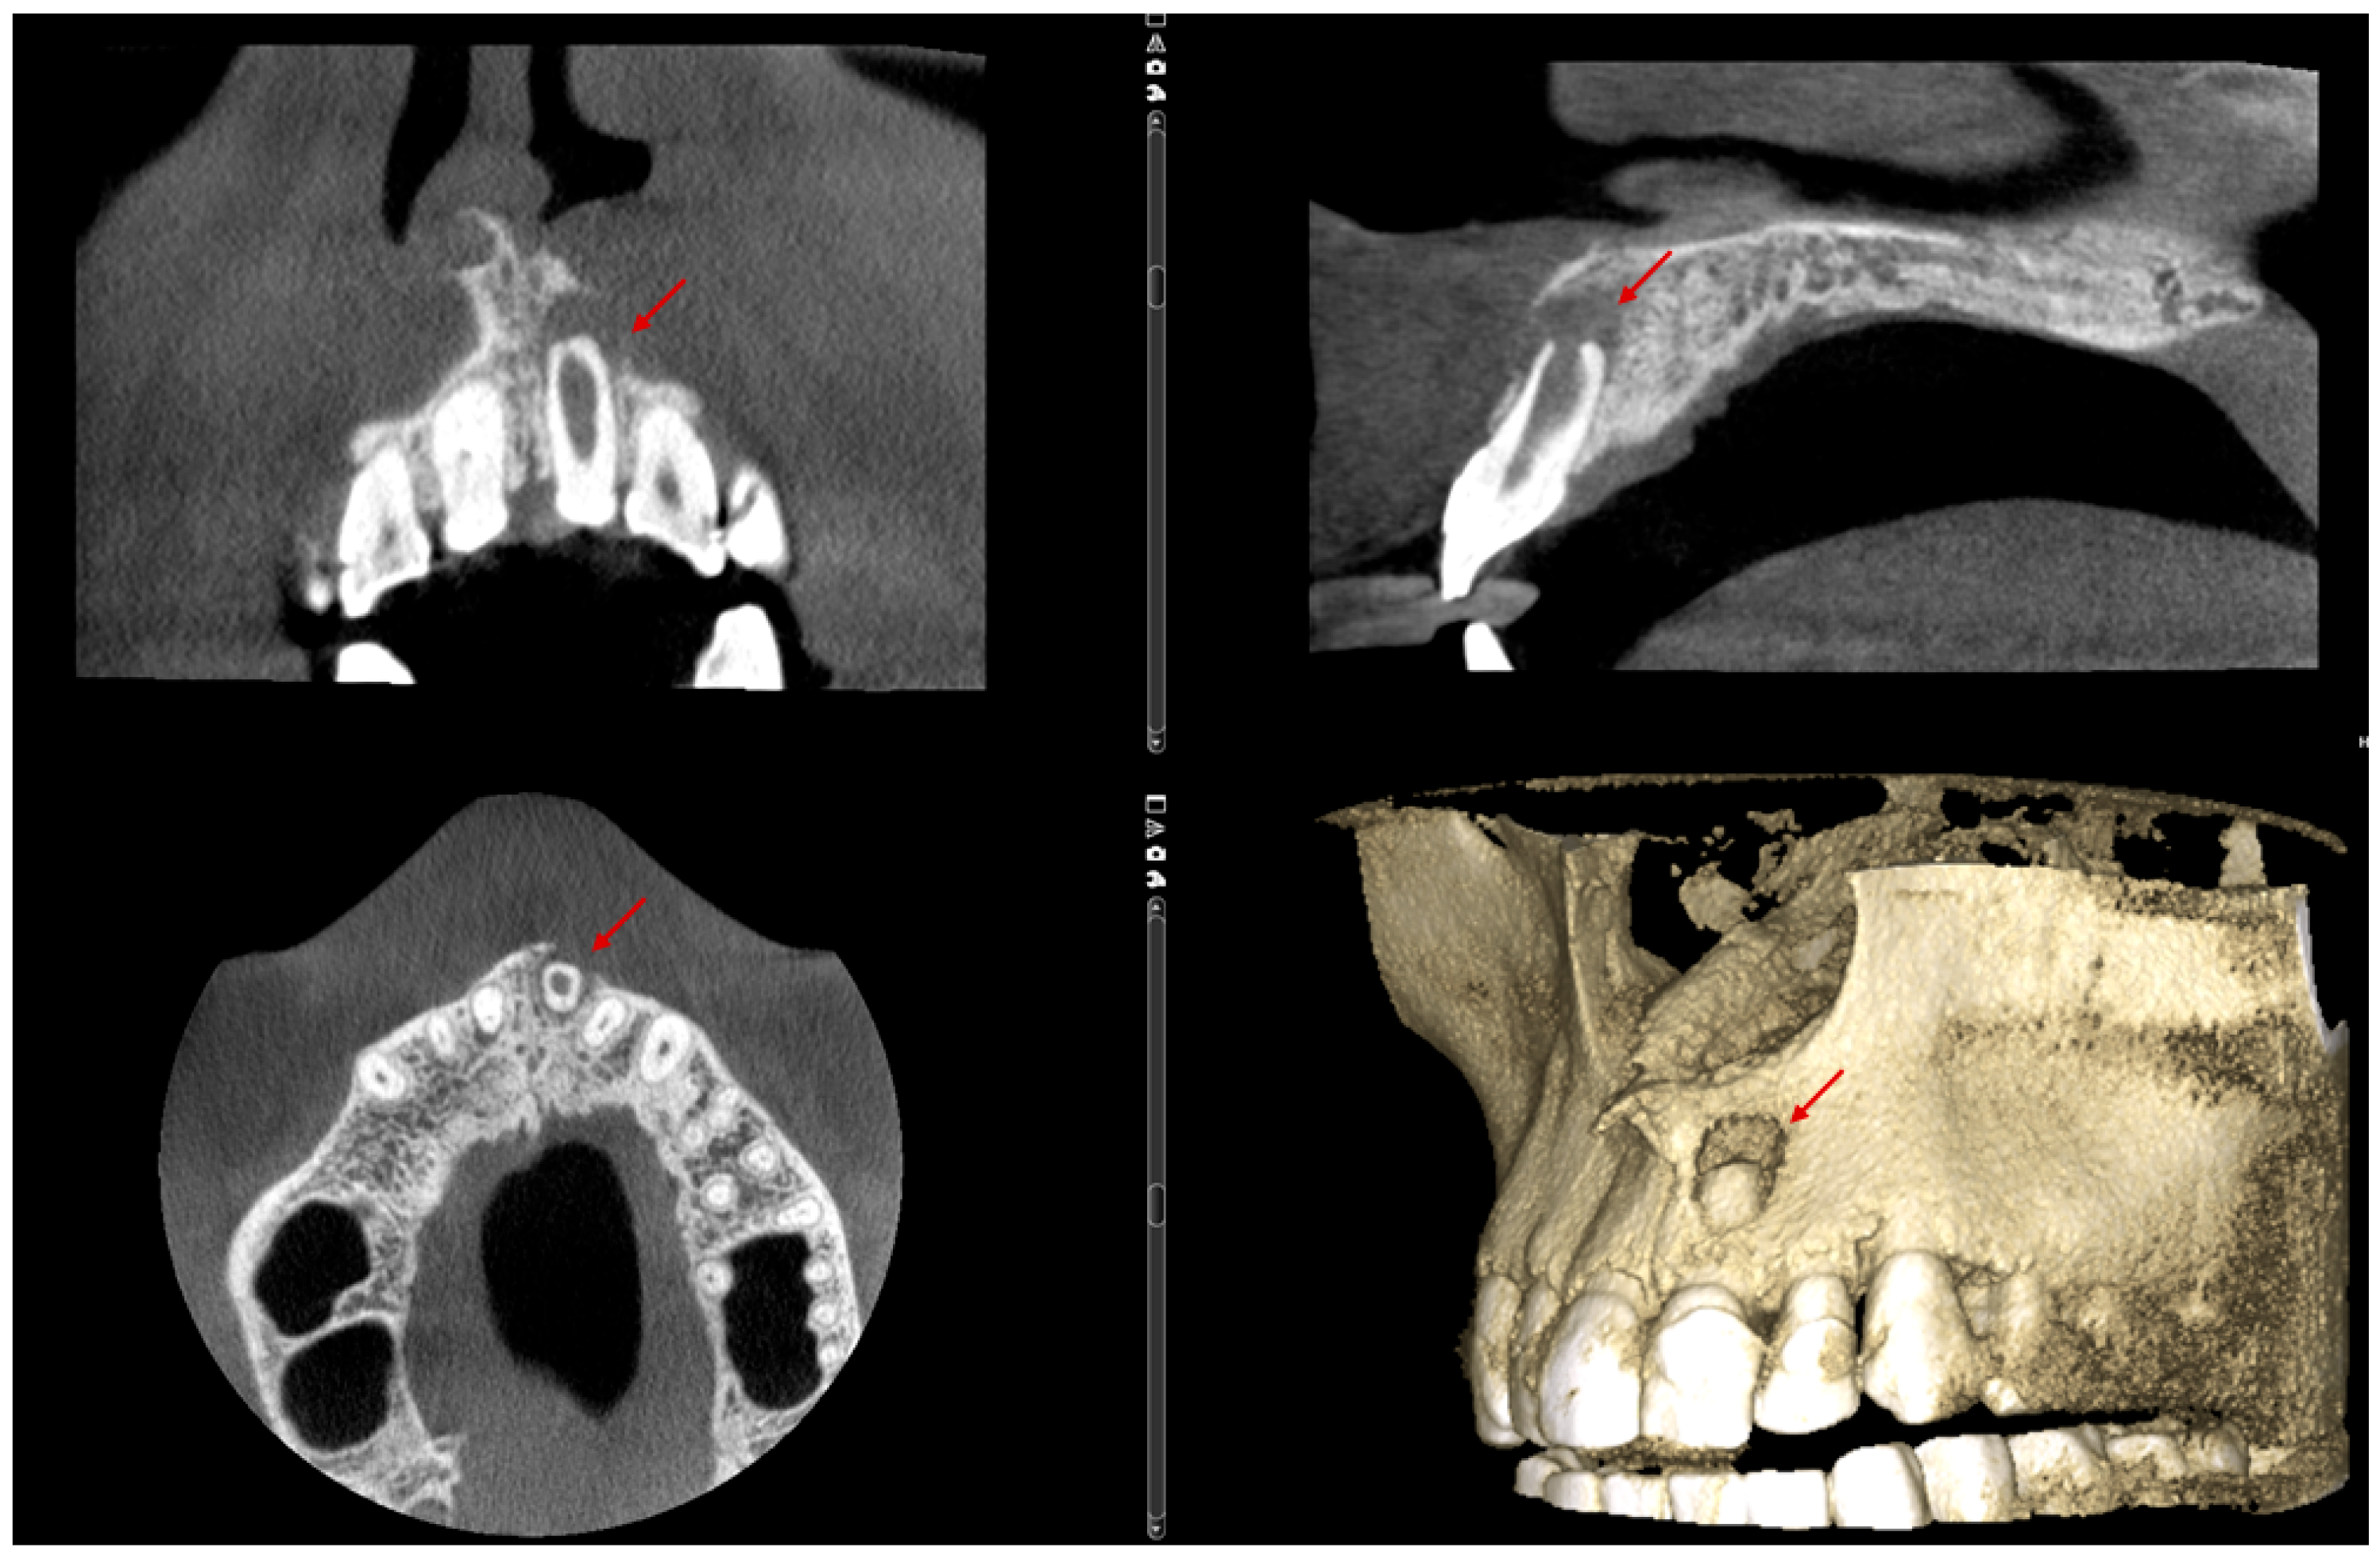

Figure 1. Preoperative radiograph of tooth #21. The radiograph shows previous endodontic treatment, with the root canal filling material not extending to the full length of the canal. A diffuse radiolucency is visible around the open apex. (The mark in the lower left corner indicates the left side).

The periapical radiograph showed that tooth #21 had undergone previous endodontic treatment. A diffuse periapical radiolucency was observed surrounding the open apex. Additionally, the root appeared relatively short and exhibited thinner dentinal walls compared to the adjacent tooth #11 (Figure 1).

Figure 2. Radiographic verification of the working length confirmed accurate measurement during the clinical appointment. (The mark in the lower left corner indicates the left side.)

The working length was confirmed radiographically using an ISO size 80 gutta-percha cone (DiaDent, Cheongju, South Korea). Following this, the gutta-percha was removed, and calcium hydroxide dressing (Calcipast, Cerkamed, Stalowa Wola, Poland) was placed in the canal and left in situ for a period of two weeks (Figure 2).